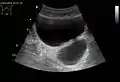

• Bladder diverticula are balloon-like growths on the bladder commonly associated with chronic outflow obstruction, such as benign prostatic hyperplasia in older males. Usually found in pairs on opposite sides of the bladder, bladder diverticula are often surgically removed to prevent infection, rupture, or even cancer.